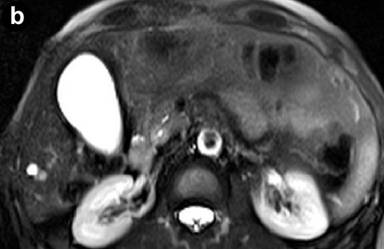

MR imaging was successively performed to evaluate and characterize the nature of the biliary stenosis by acquiring axial and coronal T1- and T2-weighted with/without fat saturation images integrated with MRCP T2-weighted hydro-cholangiographic sequences. In particular, the patient received 900 mL of superparamagnetic oral contrast material (Lumirem®, Guerbet, Paris, France) 20 min before the study. Post-contrast acquisition was performed after the intravenous administration of gadolinium diethylenetriamine pentaacetic acid (DTPA) in a volume of 20 mL with 2 mL/s acquiring T1 fast-field echo short-time inversion recovery (FFE-STIR) images. In particular, cross-sectional T1- and T2-weighted and MR cholangiography sequences showed dilatation of the biliary tree including the intrahepatic ducts, primarily of the left hepatic lobe and the common hepatic duct. Furthermore, MR images showed a lengthy stricture with luminal flow-signal preserved, irregular margins as well as abrupt and asymmetric narrowing in the middle third and intra-pancreatic segment of the common bile duct (Figure 1). A solid lesion along the common bile duct, at same level of the stricture, appearing as circumferential wall-thickening with a firm component projecting into the duct lumen, was also detected (Figure 2); after the administration of contrast medium, the lesion did not show significant enhancement in the arterial phase; however, late-phase images showed non-homogeneous enhancement (Figure 3). There was no evidence of positive lymph nodes or metastatic disease; the characteristics of the MR images were suggestive of a malignant primary stenosis probably by extra-hepatic cholangiocarcinoma. Furthermore, MR views demonstrated mild enlargement of the pancreas associated with a non-homogeneous signal intensity of the pancreatic tissue due to the presence of a hypointense nodule (Figure 3). A second ERCP examination was subsequently performed, which revealed a stricture immediately above and at the level of the intra-pancreatic common bile duct and the biliary stent was removed; brush cytology did not reveal atypical cells and the final report was not indicative of malignancy.

Figure 2. Cross-sectional T2-weighted fat-suppressed images. Axial T2-weighted turbo spin eco short-time inversion recovery (STIR) sequences show a circumferential wall-thickening of the common bile duct with a firm component projecting into the lumen. |

Figure 3. T1-weighted fast-field echo short-time inversion recovery (FFE STIR) post-contrast image shows a solid lesion with inhomogeneous late-phase enhancement (at the level of the intra-pancreatic biliary tract); moreover, MRI demonstrates mild enlargement diffusely involving the head of the pancreas associated with inhomogeneous signal intensity of the pancreatic tissue due to the presence of a hypointense nodule (arrow). |